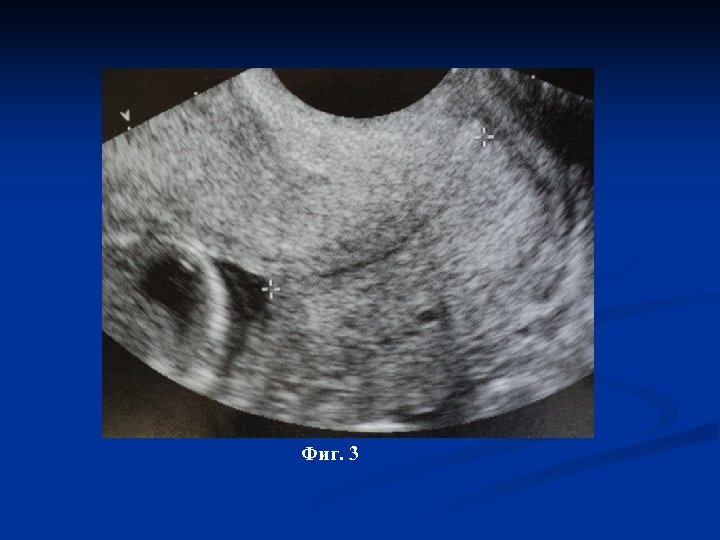

Dist – 1, 80 cm Фиг. 2